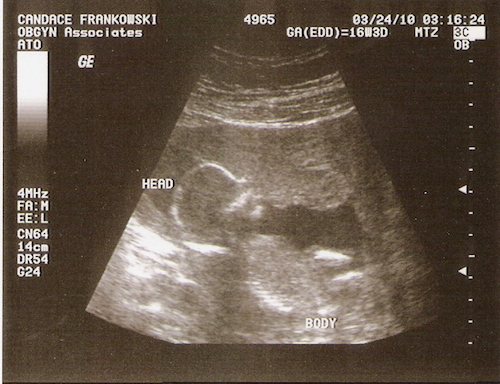

We were expecting our Maddie to come into our lives in September of 2010, when a doctor appointment at 36 weeks completely turned our world upside down. The doctor could not find Maddie's heartbeat. We were rushed to Mercy hospital where another doctor confirmed that our first baby was no longer living. I can clearly remember every sound, every smell and every single second of those 24 hours. It was the worst day of me and my husbands lives. The first time I laid eyes on her I knew I had never seen anything more beautiful in my life. I will always remember the day that I spent with her and am so happy that we decided to do so. The next few days were surreal as we planned her memorial and burial services. Although we never got to meet her in person, it was the hardest thing we have ever had to do.